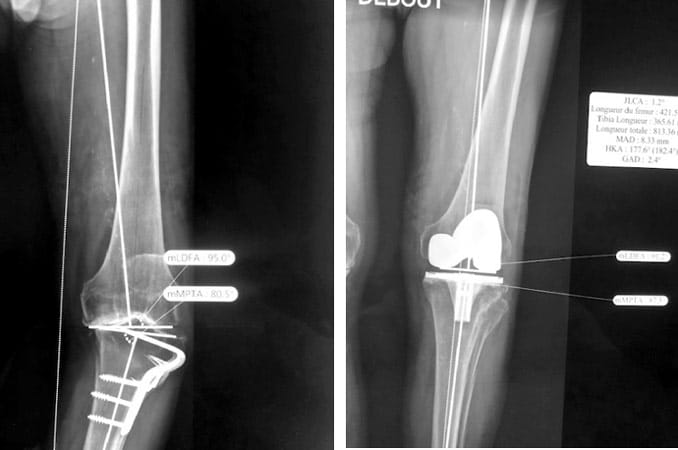

Homme de 75 ans ; fracture du fémur il a 50 ans ; consolidation avec cal vicieux de 27°.

Artrhrose interne ; douleur + boiterie + raccourcissement de 3 centimètres.

Indication de prothèse totale du genou Postéro-stabilisée associée dans le même temps à une ostéotomie fémorale de valgisation par soustraction externe fixée par une plaque.